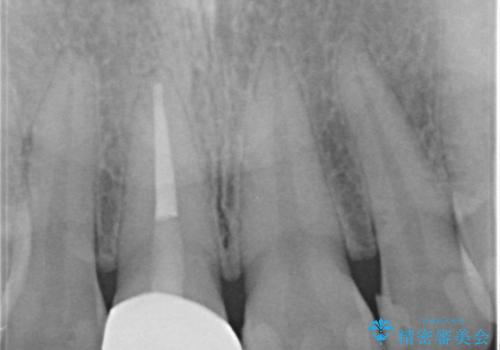

- 前歯一本だけ色が暗いことが気になりご相談にいらした患者様です。周辺の歯と色味をぴったり合わせることで自然な仕上がりになりました。

- 16万円(精密根管治療は別途)費用は治療当時の料金となります

根管治療をした歯は神経のある歯と比較して強度が下がり、長期的に破折のリスクが高まると言われています。破折のリスクを軽減させるため、根管治療を行った歯に対しては歯冠をすべて覆うクラウンという被せ物にて補綴処置を行います。

適合不良の補綴物は二次的な虫歯発生のリスクが高まります。

自費診療で用いられる材料は保険適応の材料に比べて、より精密で適合の良い被せ物作ることができるため、長期的な虫歯のリスクを大幅に減らすことが可能です。